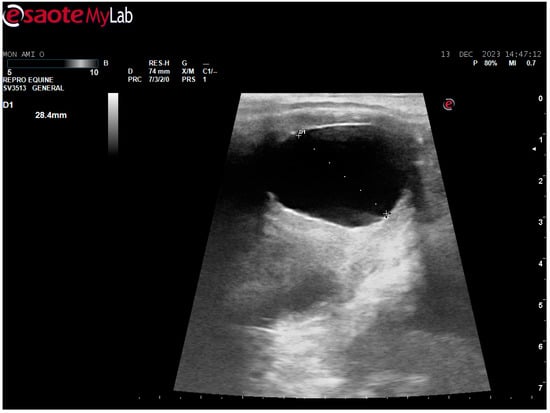

After surgery, the mare’s reproductive system was investigated. Ultrasonographically, slight uterine edema (grade 1 out of 5) and hyperechoic particles (Figure 2), suspected as air in the uterus, were observed. The left ovary was normal in size and echogenicity, present with some 10 to 28.4 mm follicles (Figure 3 and Figure 4). Due to poor perineal conformation, the mare had pneumovagina. Caslic’s vulvoplasty was performed.

Figure 4. Left ovary, present with 28.4 mm follicle follicles. Ultrasonographic picture post surgery.

Animals 14 01307 g004